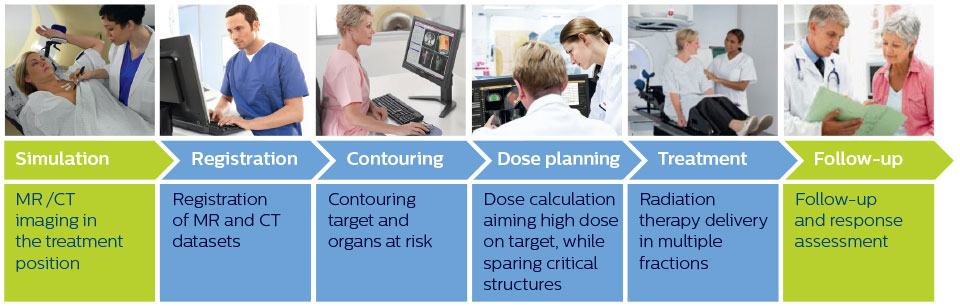

Simplified overview of MR imaging in radiation therapy workflow

Imaging plays a vital role at several steps in the radiation therapy workflow to visualize targets and critical structures for contouring, and to assess treatment response.